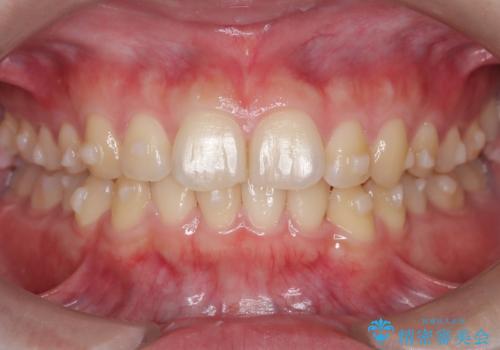

マウスピース矯正で前歯のガタツキを改善! 短期間で治療完了

- 1年3ヶ月

- 10-30回